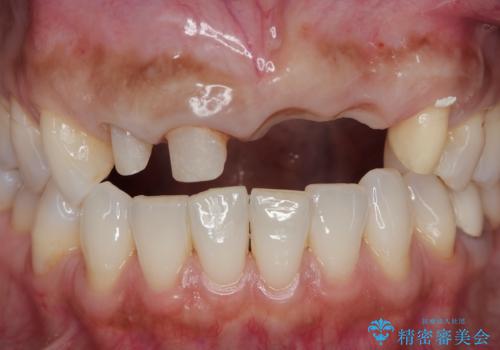

- 前歯がグラグラし、においもする、とのことで改善を求めて来院されました。

一見して問題ないように見える左側の2前歯は、セラミックを除去してみると亀裂や虫歯の再発が見られました。

抜歯時に可及的に歯肉のボリュームを保つよう骨充填材とコラーゲン製剤による填塞を行い審美的かつ機能的なブリッジとなるよう治療を進めます。

一件綺麗に見えるセラミックも適合や精度が悪いと、内部で虫歯が進行し亀裂や破折、悪臭の原因となることがあります。